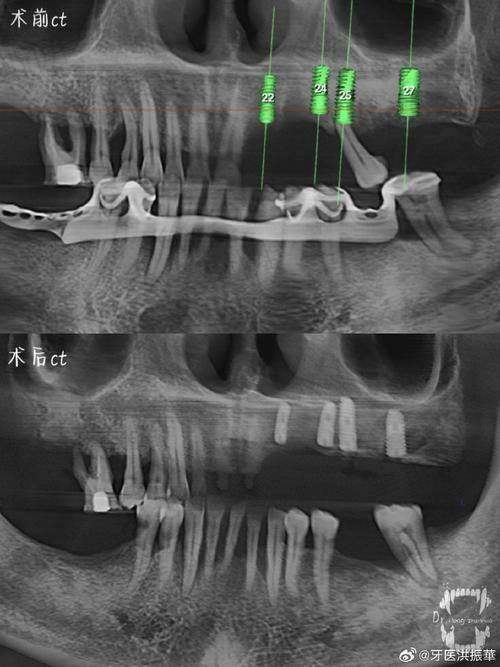

技術特色:用AI 3D模擬種植成效(術前可以睇到種完之後啲牙點樣,香港都少有呢個技術),全口種植係強項,但種植牙橋实例相對少啲。